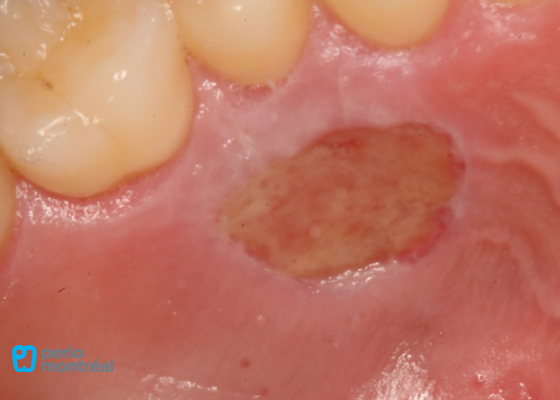

The recipient site is prepared following root planing of tooth #41 to decrease the root convexity. The donor tissue is harvested from the right palate.